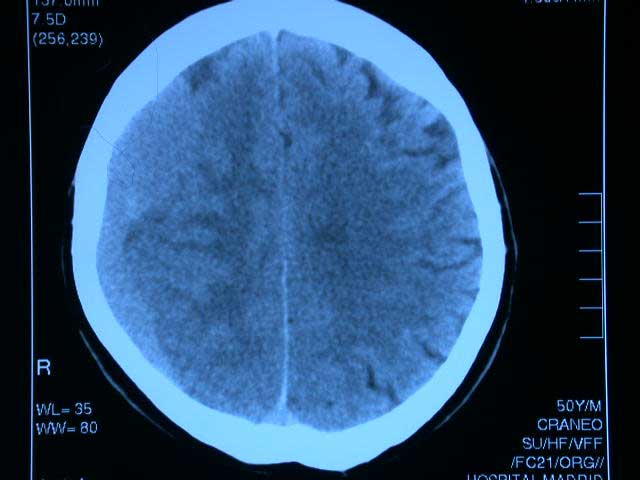

Fármacos antitrombóticos y hematoma subdural

01 marzo 2017

El uso creciente de fármacos anticoagulantes y antiagregantes se asocia a un aumento de hematomas subdurales, especialmente en los mayores de 75 años. La combinación de antagonistas de vitamina K con antiplaquetarios potencia el riesgo. JAMA, 28 de febrero de 2017